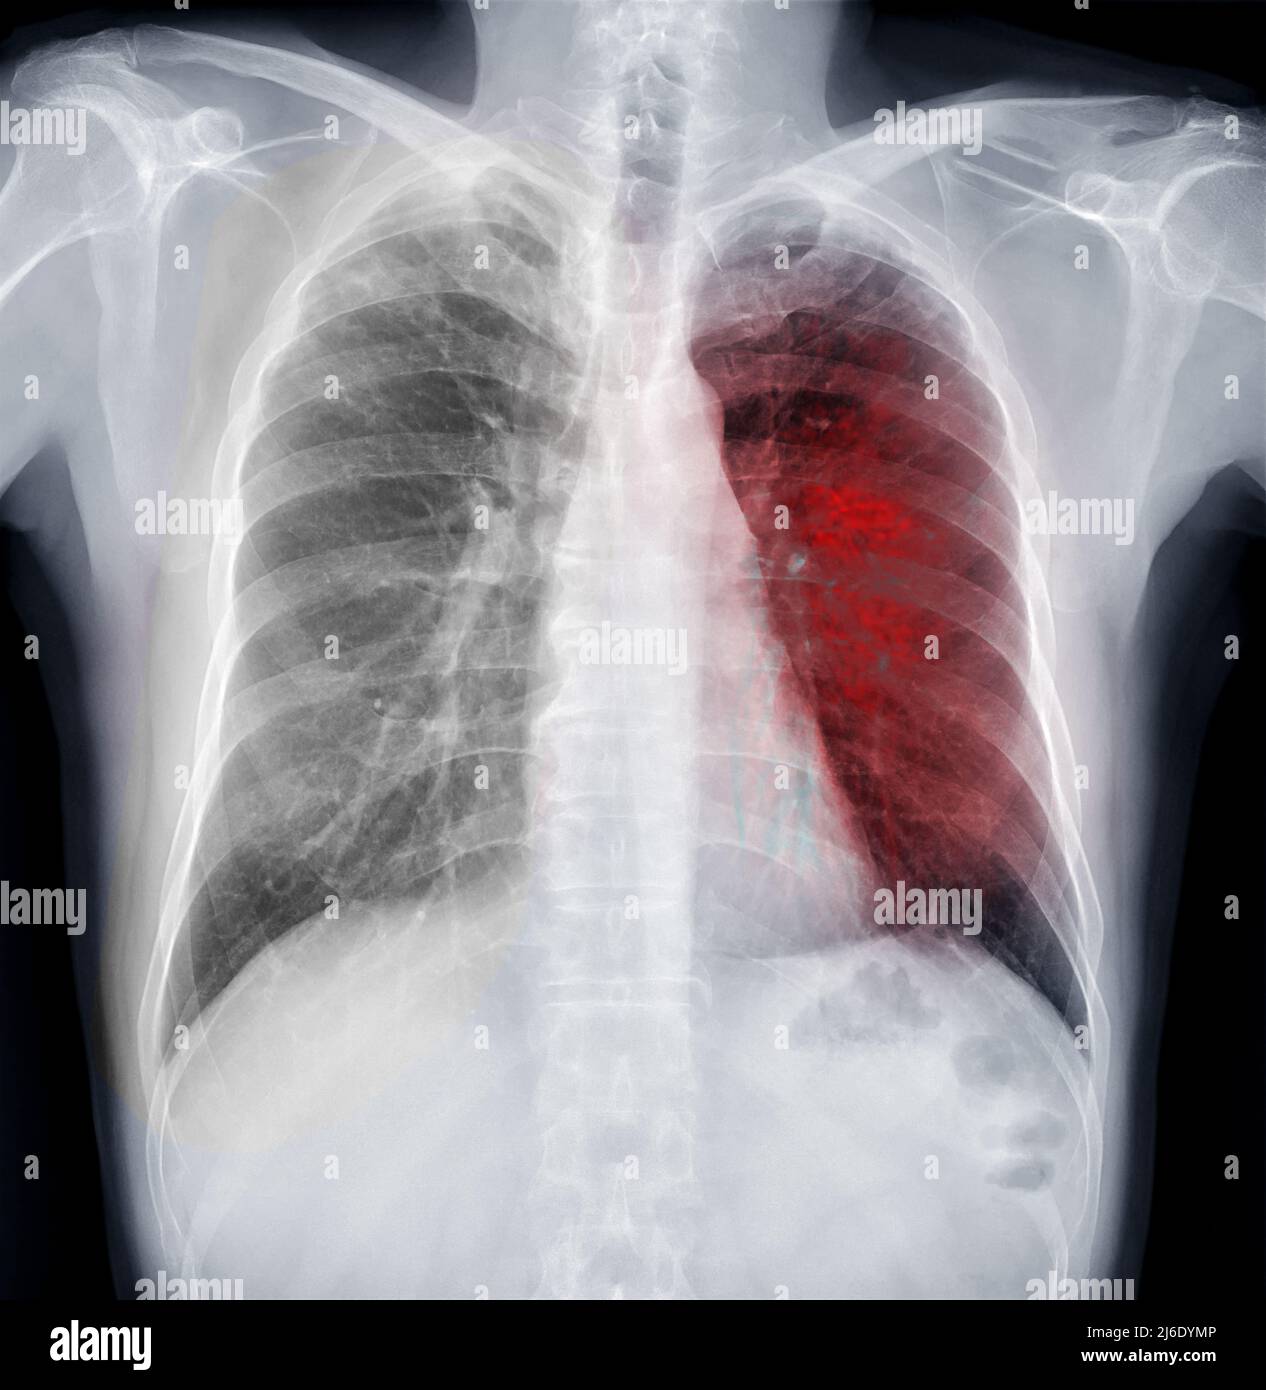

Chest Xray for tuberculosis (TB) What to expect, results, and more

Can Chest X Ray Detect Tb . This may show signs of cavitation, pleural effusion, mediastinal or hilar lymphadenopathy, or parenchymal. Your health care provider will do other tests to determine if you have inactive tb or. a positive test result for tb infection means you have tb germs in your body. in addition, ct of the chest has the potential to detect features of extrapulmonary tb.

Chest Xray Of Human Chest or Lung for detect tuberculosis Stock Photo Can Chest X Ray Detect Tb Your health care provider will do other tests to determine if you have inactive tb or. This may show signs of cavitation, pleural effusion, mediastinal or hilar lymphadenopathy, or parenchymal. a positive test result for tb infection means you have tb germs in your body. in addition, ct of the chest has the potential to detect features of. Can Chest X Ray Detect Tb.